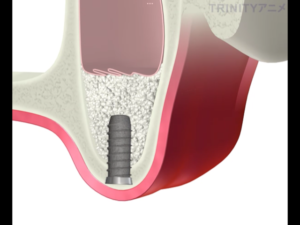

骨を盛り上げた部分にインプラントを埋入します。

実際の処置後です。

下の歯と本数を揃えるため、計画を再立案し3本のインプラントを埋入しました。

インプラントの上にドーム状に広がっているのがサイナスリフトを行い填入された人工骨です。

予定通りの場所に、予定通りの方法でインプラント手術を終えることができました。

ここから、人工の骨が安定し既存の骨と一体化するまで8ヶ月ほど待ち、被せ物の作製をしていきます。

サイナスリフトを行うことで通常のインプラント治療に比べ待つ期間は長くなりますが、骨の厚みが増え長期的にインプラントが安定できる状態になります。